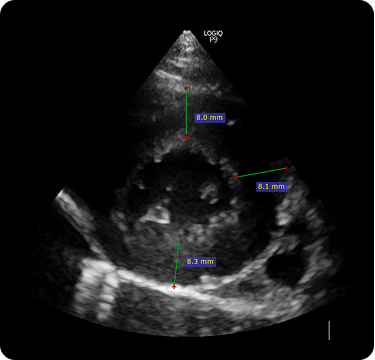

일반적으로 심근질환의 진단은 혈액검사를 통한 평가와 흉부방사선검사 심장초음파 검사를 통해 평가를 하게 됩니다.

형태 평가를 위한 방사선 검사 및 심장 초음파 검사가 중요합니다.

좌심실 벽이 전반적 혹은 국소적으로 두꺼워진 상태를 이야기합니다.

고양이에서 가장 흔하게 진단되는 심근질환으로 심장(특히 좌심실)의 벽이 두꺼워져 심실 내강이 좁아지고 질병의 진행에 따라 이차적인 좌심방 확장이 동반됩니다. 이로 인해 심장 기능이 저하되고, 혈전/심부전/급사의 위험이 발생하게 되는 질환입니다.